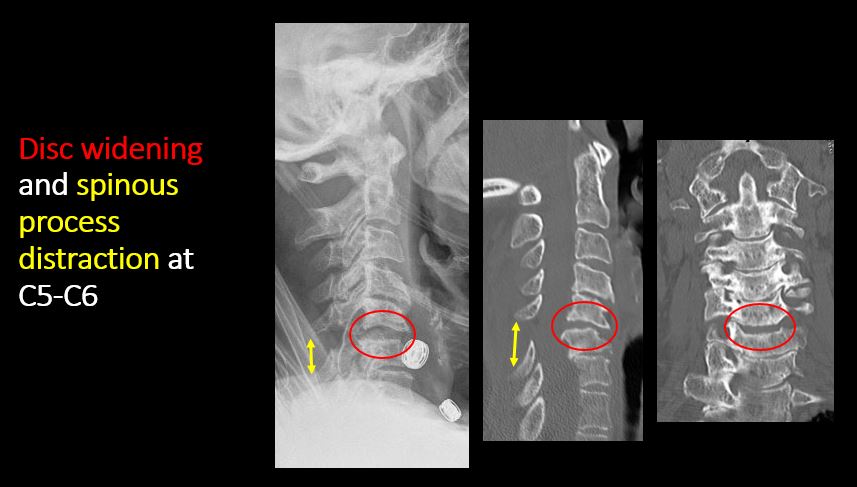

Section 1 Submit Findings C442 Findings Technique The craniocervical junction and/or C7-T1 are not entirely included on the exam. Yes No The exam is over or under penetrated. Yes No The exam is limited by overlying structures, bones or soft tissues, body habitus, patient positioning, support devices, or motion. Yes No Prevertebral and paravertebral soft tissues The soft tissues anterior to C1-C7 are widened or the prevertebral fat stripe is not seen. Yes No The paravertebral soft tissues are abnormally widened. Yes No N/A There is calcification, foreign body, abnormal air, or other abnormal density in the prevertebral or paravertebral soft tissues. Yes No Spinal alignment The distance between the basion and the posterior axial line is > 12 mm. Yes No The distance between the basion and the tip of the dens is > 12 mm. Yes No The atlanto-axial joint distance is > 2 mm on the lateral view. Yes No The distance between the dens and the lateral masses of C1 is abnormally asymmetrically widened on an odontoid or AP view. Yes No N/A The lateral mass(es) of C1 abnormally override(s) the articular pillar(s) of C2 on an odontoid or AP view. Yes No N/A The anterior vertebral body line, posterior vertebral body line, articular pillar line, and/or spinolaminar line is/are abnormal. Yes No The articular pillars or lateral masses, lamina, or other posterior elements are rotated or displaced into the spinal canal or the interlaminar clear zone of the spinal canal. Yes No The visualized spinous processes are malaligned on the AP view or distracted on the lateral view. Yes No There is reversal or straightening of the normal lordosis or abnormal angulation/curvature or motion of the cervical spine on frontal, lateral, flexion and/or extension views. Yes No Vertebral bodies, posterior elements, and base of skull There is a fracture or deformity of the base of the skull or occipital condyles. Yes No There is a fracture or deformity of the anterior or posterior arch of C1. Yes No There is a fracture or deformity of the lateral mass(es) of C1. Yes No There is a fracture or deformity of the dens or C2 vertebral body. Yes No There is a fracture or deformity of the pars interarticularis/articular pillars or other posterior elements of C2. Yes No There is a fracture or distraction of a C3-T1 vertebral body, transverse or spinous process, or other posterior element. Yes No There is evidence of an end plate avulsion or other fracture. Yes No There is displacement of a fracture fragment into the soft tissues, spinal canal, or interlaminar clear zone of the spinal canal. Yes No There is anterior wedging or compression of a vertebral body or end plate. Yes No There is evidence of an aggressive disease process manifest as a lytic, sclerotic, or destructive abnormality of a vertebral body, end plate, pedicle, lamina, articular pillar, transverse or spinous process. Yes No There is focal or diffuse abnormal mineralization. Yes No Disc spaces and facet joints There is distraction or focal widening of a disc space. Yes No There is anterolisthesis, retrolisthesis, subluxation, or rotational abnormality of a disc space. Yes No There is widening, rotational abnormality, or displacement of facets at any motion segment (e.g. locked or jumped, perched facets, or fracture dislocation). Yes No There is disc space narrowing with or without erosive or sclerotic changes of the end plates other than from degenerative change. Yes No There is facet joint narrowing or sclerosis other than from degenerative change. Yes No Additional soft tissues and bones (neck, airway, upper thorax, ribs) The included maxillofacial region, thoracic spine, ribs, or other bones of the upper thorax are abnormal. Yes No There is air or a foreign body or other abnormality in the soft tissues of the lower head, neck or upper thorax. Yes No There is an apical mass, thickening, pleural cap or effusion, or pneumothorax. Yes No N/A The airway is narrowed or displaced. Yes No There are post surgical changes of the bones or soft tissues of the lower head, neck, or upper thorax. Yes No There is an abnormality or complication of post-surgical hardware. Yes No N/A There are support lines or tubes in an abnormal position. Yes No Other findings There are degenerative changes or other existing conditions that might be contributing to symptoms which can or should be further evaluated non-emergently. Yes No